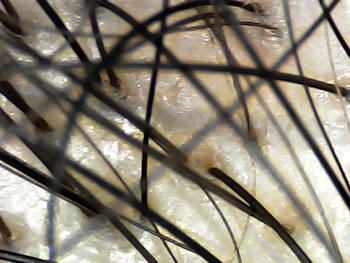

22-year-old hair loss.. I took it under a scalp microscope. Help mecrying

I had a lot of hair when I was young, but due to stress on entrance exams and less drying my hair, I felt that the top of my head became very empty from last spring

Then, last winter, seborrheic scalp infection occurred, and now I don't have it, but I still have a feeling of heat, itchiness, and dandruff.

I bought a scalp microscope and took a picture of it, and there is a lot of hair with just one strand on the hair follicle and the scalp around the top of the head is usually red and yellow..

1. The hair on the top of the head has really decreased a lot.